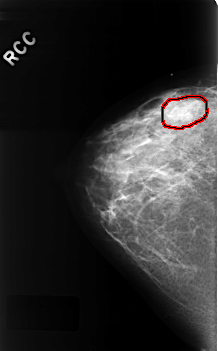

C_0330_1.RIGHT_CC

FILE: C_0330_1.RIGHT_CC.OVERLAY

TOTAL_ABNORMALITIES 1

ABNORMALITY 1

LESION_TYPE MASS SHAPE LOBULATED MARGINS OBSCURED

ASSESSMENT 3

SUBTLETY 2

PATHOLOGY BENIGN

TOTAL_OUTLINES 1

BOUNDARY